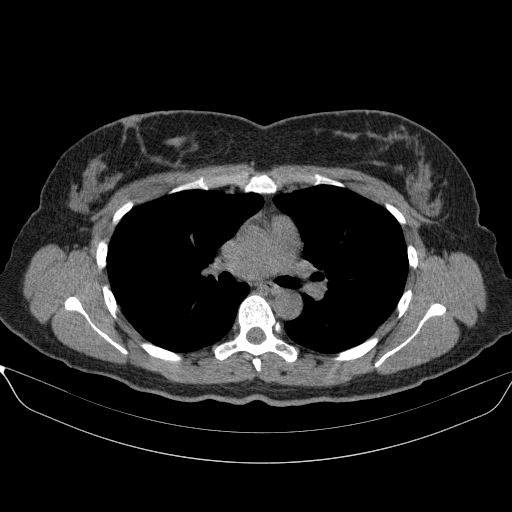

Generated VENOUS CT scan (A→B translation)

Full window (WL 1023.5, WW 4095 β†’ Low βˆ’1024, High +3071)

Actual HU range: [-1024.0, 1442.8]

Lung window (WL -600, WW 1500 β†’ Low βˆ’1350, High +150)

Actual HU range: [-1193.4, 150.0]

Mediastinum window (WL 40, WW 400 β†’ Low βˆ’160, High +240)

Actual HU range: [-160.0, 240.0]